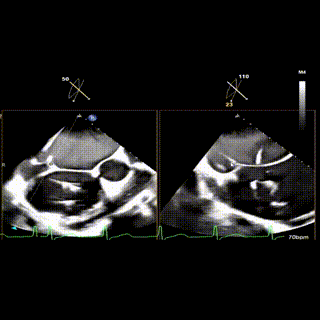

术前TEE评估

术前瓣膜介入团队的心超医生陈星星医师王良国医师对患者的心脏结构和瓣膜解剖情况进行详细的评估:

1.二尖瓣重度关闭不全(4+),瓣环明显扩大(AP径4.6cm,LM径3.9cm),扁平,关闭时瓣叶对合不佳(carpentier I),1-3区均可见反流束,返流宽度达26mm;肺静脉频谱呈收缩期反向。

2.画迹法测得二尖瓣瓣口面积约8.8cm²。

3.PISA法测得EROA=0.57cm²,Rvol=77ml,r=11mm。

4.二尖瓣前叶(A2)长度29mm,后叶(P2)长度11mm。

5.左房巨大(三径86*84*114mm),右房巨大(内径114*86mm),CFI提示极重度三尖瓣反流,Teich法测得EF为70.1%。

怎么上穿刺鞘攻克巨大左房伴转位穿刺难关!温医大附一院周浩教授团队创新应用“导丝定位+可调弯鞘”技术完成高难度TEER手术_https://www.jmylbn.com_新闻资讯_第2张

1区

怎么上穿刺鞘攻克巨大左房伴转位穿刺难关!温医大附一院周浩教授团队创新应用“导丝定位+可调弯鞘”技术完成高难度TEER手术_https://www.jmylbn.com_新闻资讯_第3张

1区带彩